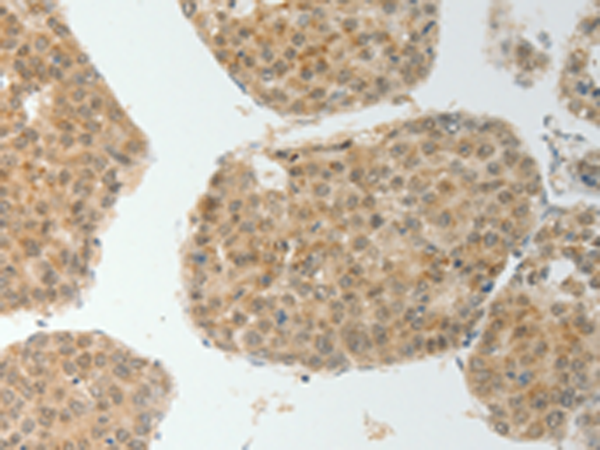

分类: 科研抗体货号: P11133别名: MTK1; MEKK4; MAPKKK4; PRO0412应用: IHC反应种属: Human